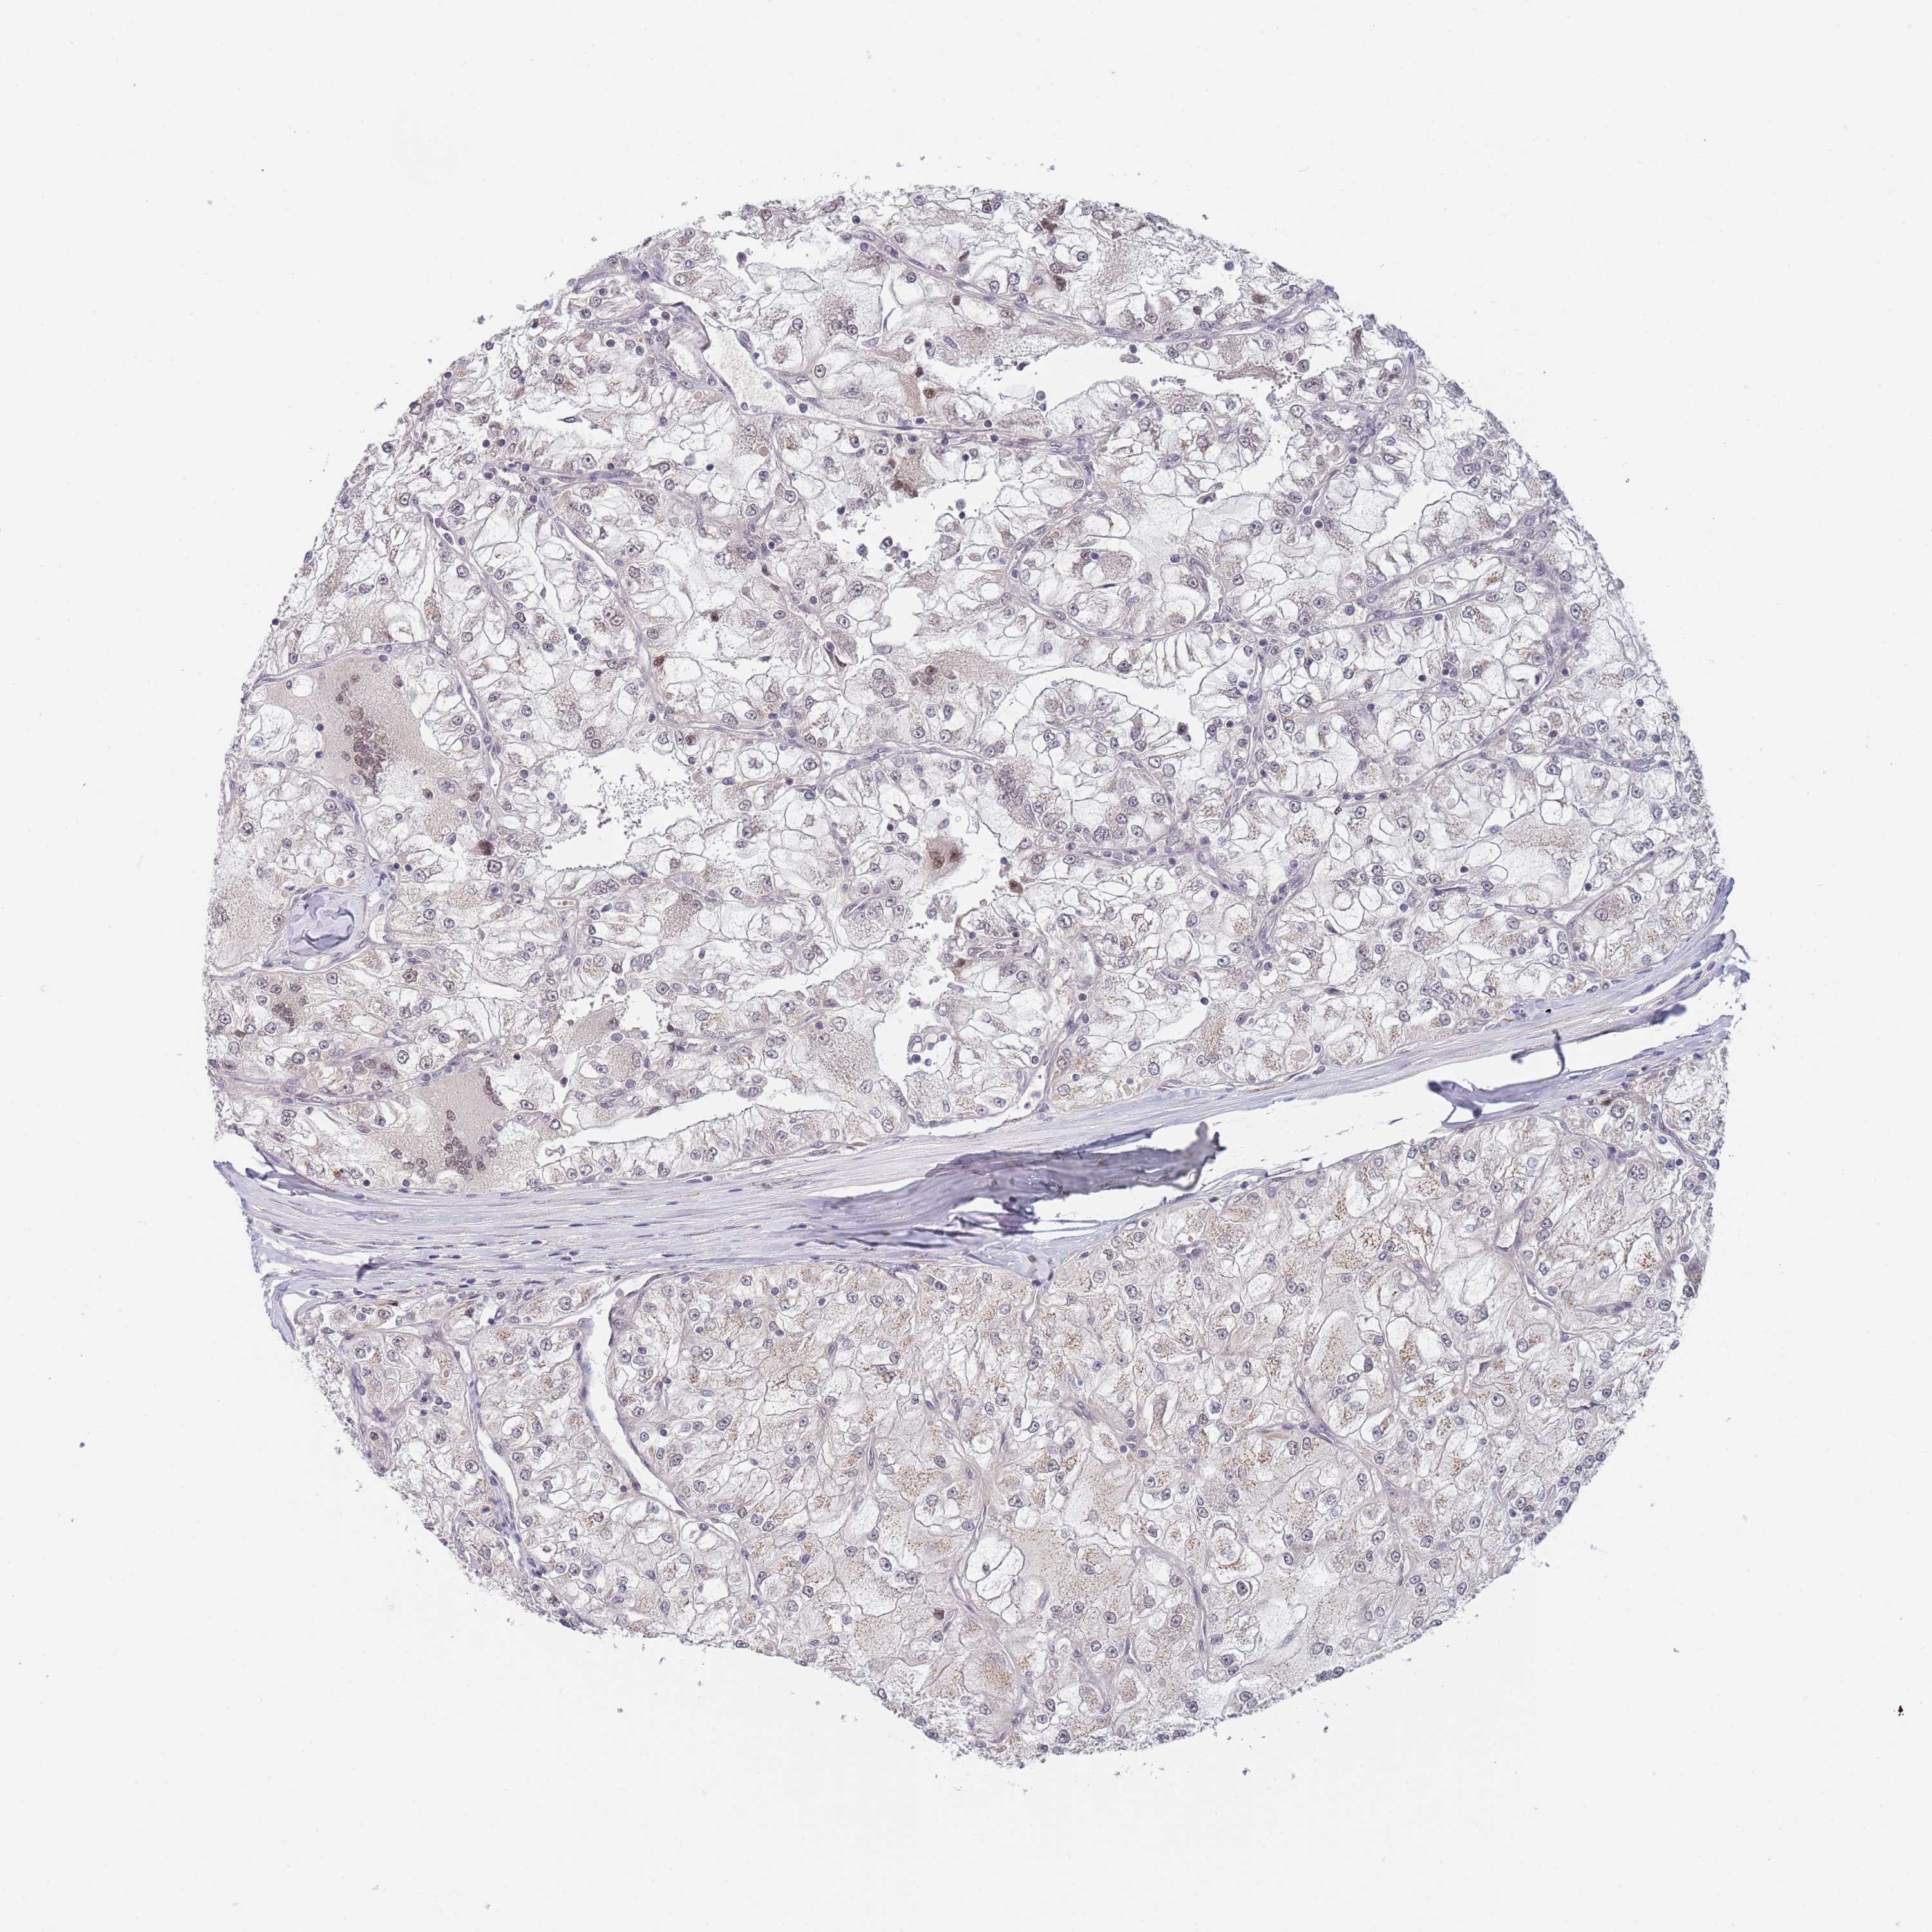

KIDNEY RENAL PAPILLARY CELL CARCINOMA (TCGA) - Interactive survival scatter ploti

The Survival Scatter plot shows the clinical status (i.e. dead or alive) for all individuals in the patient cohort, based on the same data that underlies the corresponding Kaplan-Meier plots. Patients that are alive at last time for follow-up are shown in blue and patients who have died during the study are shown in red.

The x-axis shows the expression levels (FPKM) of the investigated gene in the tumor tissue at the time of diagnosis. The y-axis shows the follow-up time after diagnosis (years). Both axes are complimented with kernel density curves demonstrating the data density over the axes. The top density plot shows the expression levels (FPKM) distribution among dead (red) and alive patients (blue). The right density plot shows the data density of the survived years of dead patients with high and low expression levels respectively, stratified using the cutoff indicated by the vertical dashed line through the Survival Scatter plot. This cutoff is automatically defined based on the FPKM cutoff that minimizes the p-score. The cutoff can be changed by dragging the vertical line or by entering a cutoff value in the square labeled "Current cut-off".

Under the Survival Scatter plot the p-score landscape (black curve; left axis) is shown together with dead median separation (red curve; right axis). Dead median separation is the difference in median mRNA expression between patients who have died with high and low expression, respectively. It is calculated as follows: median FPKM expression of dead patients with high expression - median FPKM expression of dead patients with low expression. This is intended to aid the user in visually exploring custom cutoffs and the associated p-scores and dead median separation.

Individual patient data is displayed and can be filtered by clicking on one or more of the category buttons on the top of the page. Categories describing expression level and patient information include: high, low, alive, dead, female, male and tumor stages. The scale of the x-axis can be toggled between linear and log-scale by clicking on the "x log" button. Mouse-over function shows TCGA ID, patient information and mRNA expression (FPKM) for each patient.

& Survival analysisi

Kaplan-Meier plots summarize results from analysis of correlation between mRNA expression level and patient survival. Patients were divided based on level of expression into one of the two groups "low" (under cut off) or "high" (over cut off). X-axis shows time for survival (years) and y-axis shows the probability of survival, where 1.0 corresponds to 100 percent.

B4GALT4 is not prognostic in Kidney Renal Papillary Cell Carcinoma (TCGA)